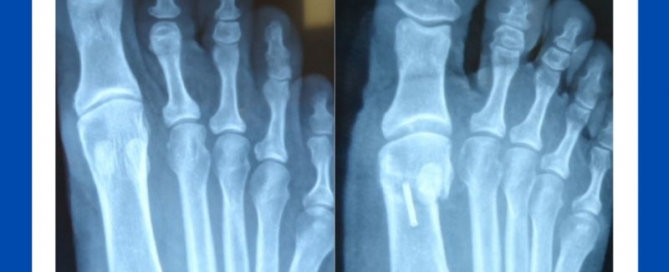

Bunion surgery: Modern procedures for quick recuperation and long-term results

Blog's main page A recent review of a very happy bunion patient. This just shows you how foot surgery has advanced over the years, particularly bunion surgery. Modern procedures allow [...]